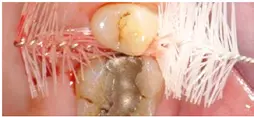

In der Praxis werden an Patienten zuweilen mit Messsonden diverse Größen ausprobiert, um eine entsprechende Empfehlung abzugeben [26]. Allerdings ist ihr Wert umstritten. Eine korrekt angepasste Interdentalraumbürste sollte den kompletten Interdentalraum reinigen und mit „mittlerem“ Druck ein- und auszuführen sein. Wenn sie zu dünn ist, hat sie eine zu geringe Reinigungswirkung; ist sie hingegen zu dick, besteht Traumatisierungsgefahr. Abbildung 2 zeigt die Einprobe und Auswahl am Beispiel des Interdentalraums 41/42.